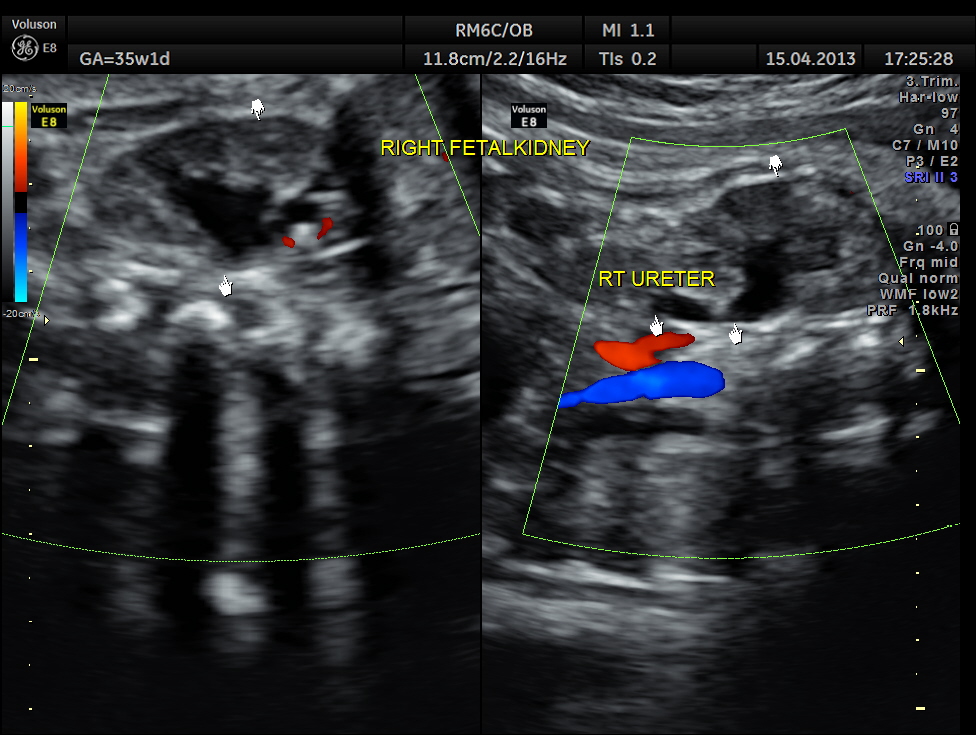

This was a 26-year-old lady with no history of consanguinity. The scan was done at 35 weeks of gestation.

Right fetal kidney shows mild pelviectasis.

Rt proximal ureter is mildly dilated

Right sided hydro uretero nephrosis , with likely obstruction at right vesico ureteric junction.